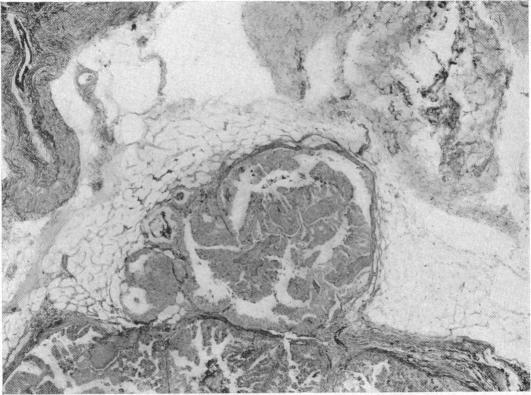

CARCINOMA OF THE THYROID.

Ann Surg. 1940 Dec;112(6):977-1005. doi: 10.1097/00000658-194012000-00001.